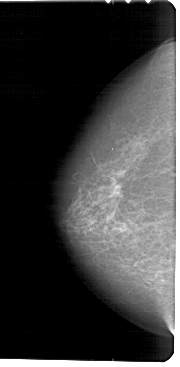

A_1457_1.LEFT_CC

LEFT_CC LINES 5491 PIXELS_PER_LINE 2686 BITS_PER_PIXEL 12 RESOLUTION 43.5 NON_OVERLAY